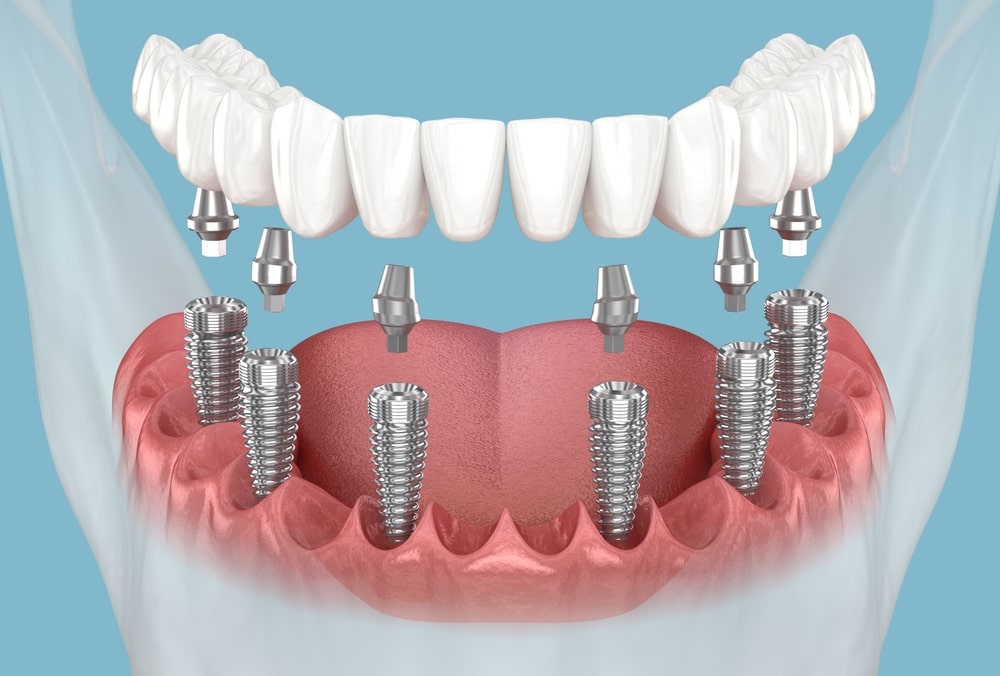

Les implants dentaires représentent aujourd’hui l’une des solutions les plus performantes pour remplacer une ou plusieurs dents manquantes. Ils se composent d’une racine artificielle, généralement en titane, insérée dans l’os de la mâchoire, sur laquelle vient se fixer une couronne ressemblant à une dent naturelle. Durables, confortables et esthétiques, les implants

Un traitement par implants dentaires est une solution moderne, durable et efficace pour remplacer une ou plusieurs dents manquantes. À Casablanca, comme partout ailleurs, ce traitement se déroule selon des étapes bien définies qui visent à garantir la réussite fonctionnelle, esthétique et biologique de l’implant.

Un traitement par implants dentaires est une solution moderne, durable et efficace pour remplacer une ou plusieurs dents manquantes. À Casablanca, comme partout ailleurs, ce traitement se déroule selon des étapes bien définies qui visent à garantir la réussite fonctionnelle, esthétique et biologique de l’implant. Comprendre chaque phase du parcours permet au patient d’être mieux informé, plus serein et de participer activement à sa prise en charge.